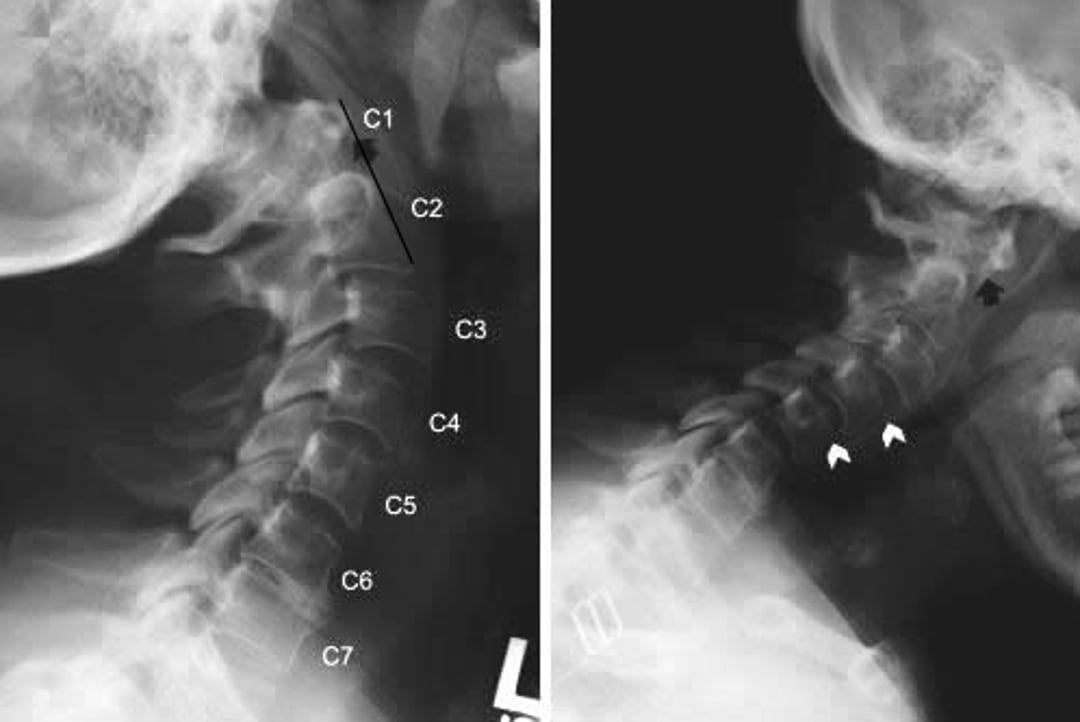

Radiografías de la columna cervical que muestran la subluxación atlantoaxoidea y la subluxación subaxial en un paciente con artritis reumatoide. Las vistas laterales de la columna cervical fueron tomadas con extensión del cuello (a la izquierda) y flexión (a la derecha). En flexión, el arco anterior de la C1 es muy anterior a la fosa de la C2 (posterior a la flecha negra), lo que indica una subluxación anterior. Este hallazgo no es evidente en extensión (flecha negra), lo que indica que la subluxación atlantoaxial es dinámica. También hay presencia de anterolistesis (deslizamiento hacia adelante del cuerpo vertebral superior, mostrado por puntas de flecha blancas) en C2-C3 y C3-C4 en extensión y en C3-C4 y C4-C5 en flexión.